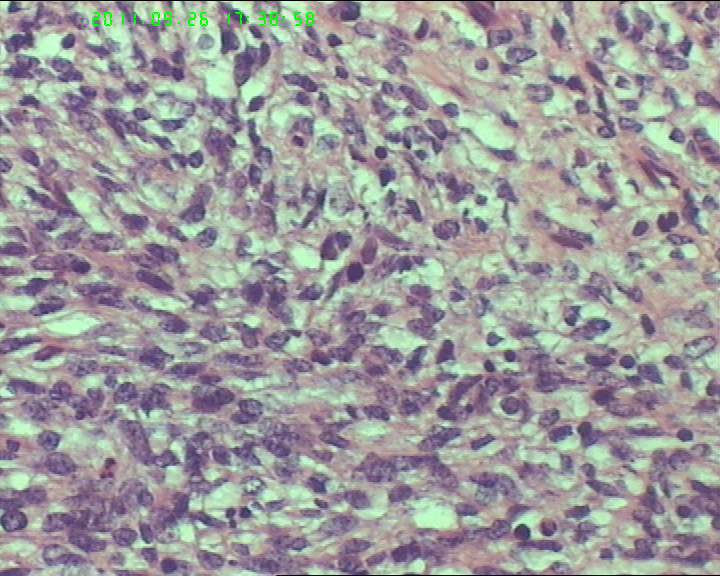

灰白不整形肿物一个,大小18*15*9cm,表面结节状,包膜完整,切面灰白,中央可见坏死区,质软,范围5*4cm。其余切面多彩 部分半透明状 质中。

鉴别诊断排排队:1、GIST,2、MPNST,3、去分化脂肪肉瘤,4、恶性间皮瘤,5、恶性SFT,6、平肉

主要考虑前二者。CD34,CD117,S-100,BCL-2,SMA, D2-40,CR, VIM. 结果如何?请楼主揭谜底吧。